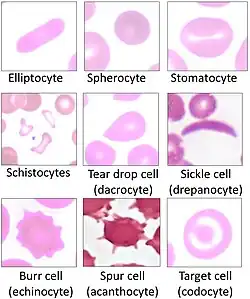

Mammals

Blood diseases involving the red blood cells include:

- Anemias (or anaemias) are diseases characterized by low oxygen transport capacity of the blood, because of low red cell count or some abnormality of the red blood cells or the hemoglobin.

- Sickle-cell disease is a genetic disease that results in abnormal hemoglobin molecules. When these release their oxygen load in the tissues, they become insoluble, leading to mis-shaped red blood cells. These sickle shaped red cells are less deformable and viscoelastic, meaning that they have become rigid and can cause blood vessel blockage, pain, strokes, and other tissue damage.

- Thalassemia is a genetic disease that results in the production of an abnormal ratio of hemoglobin subunits.

- Hereditary spherocytosis syndromes are a group of inherited disorders characterized by defects in the red blood cell's cell membrane, causing the cells to be small, sphere-shaped, and fragile instead of donut-shaped and flexible. These abnormal red blood cells are destroyed by the spleen. Several other hereditary disorders of the red blood cell membrane are known.[66]

- Hemolysis is the general term for excessive breakdown of red blood cells. It can have several causes and can result in hemolytic anemia.

- Polycythemias (or erythrocytoses) are diseases characterized by a surplus of red blood cells. The increased viscosity of the blood can cause a number of symptoms.

- Several microangiopathic diseases, including disseminated intravascular coagulation and thrombotic microangiopathies, present with pathognomonic (diagnostic) red blood cell fragments called schistocytes. These pathologies generate fibrin strands that sever red blood cells as they try to move past a thrombus.

Many diseases involving red blood cells are diagnosed with a blood film (or peripheral blood smear), where a thin layer of blood is smeared on a microscope slide. This may reveal poikilocytosis, which are variations in red blood cell shape. When red blood cells sometimes occur as a stack, flat side next to flat side. This is known as rouleaux formation, and it occurs more often if the levels of certain serum proteins are elevated, as for instance during inflammation.